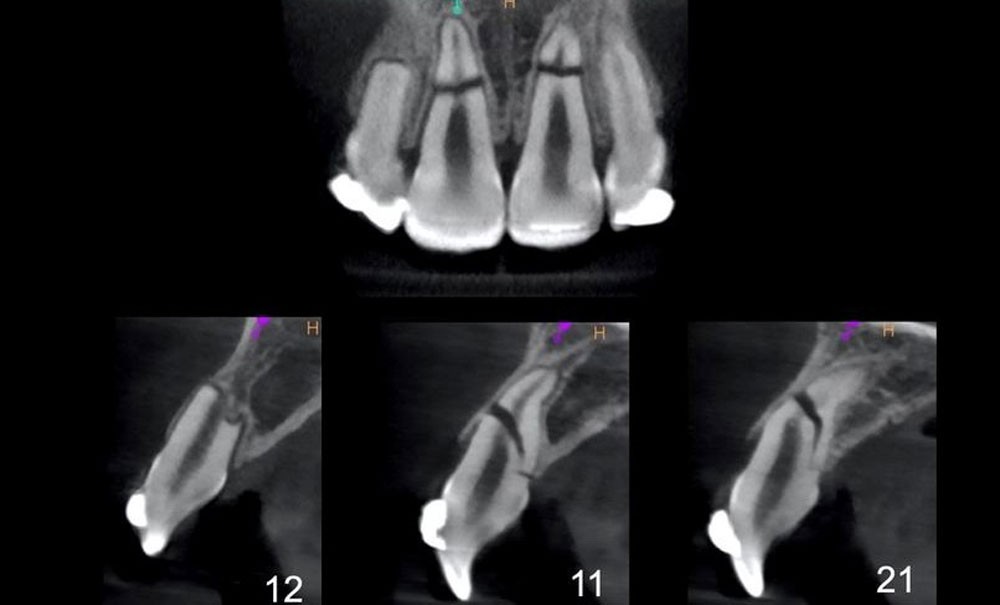

Lors de ce deuxième rendez-vous, un CBCT est prescrit et met en évidence l’étendue des fractures ainsi que le repositionnement inadéquat des deux fragments coronaires des dents 11 et 21 (fig. 3).